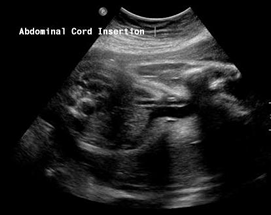

Above. Urachal cyst. Note the anechoic connection between the fetal bladder and the umbilicus.